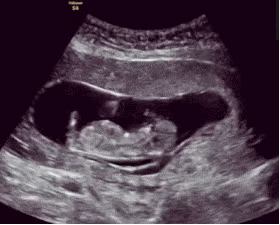

胎儿是很聪明的,一般从怀孕四个月起,胎儿就有了敏感的听觉,所以孕中期可以开始做胎教,刺激胎儿的听觉神经发育。

胎儿的听觉系统在孕期就已经发育,胎儿在孕六个月的时候,能听到外界的声音,包括妈妈的说话声,呼吸声。所以,孕期做胎教还是很有必要的,而且胎儿能感觉到,但并不一定能完全理解胎教中的全部意思。

我是二胎妈妈,孕期6个月的时候就明显感觉到胎宝宝对声音很敏感。每次播放胎教音乐的时候,胎儿就会随着音乐动起来,可以感觉到宝宝很兴奋。原来,4个月的时候胎儿听觉器官已初步发育完全,但对接收外界声音还是比较模糊,但到了第6 个月时,胎宝宝的听力就与成人无异了,真的是神奇。